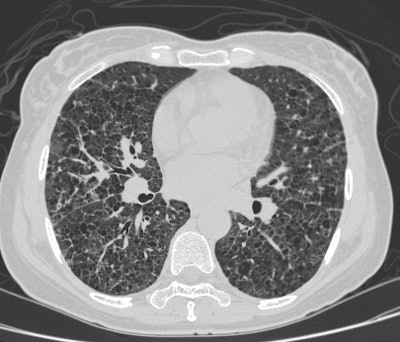

HRCT exam revealed diffuse cystic changes throughout the lungs. Open lung biopsy revealed LCH. |